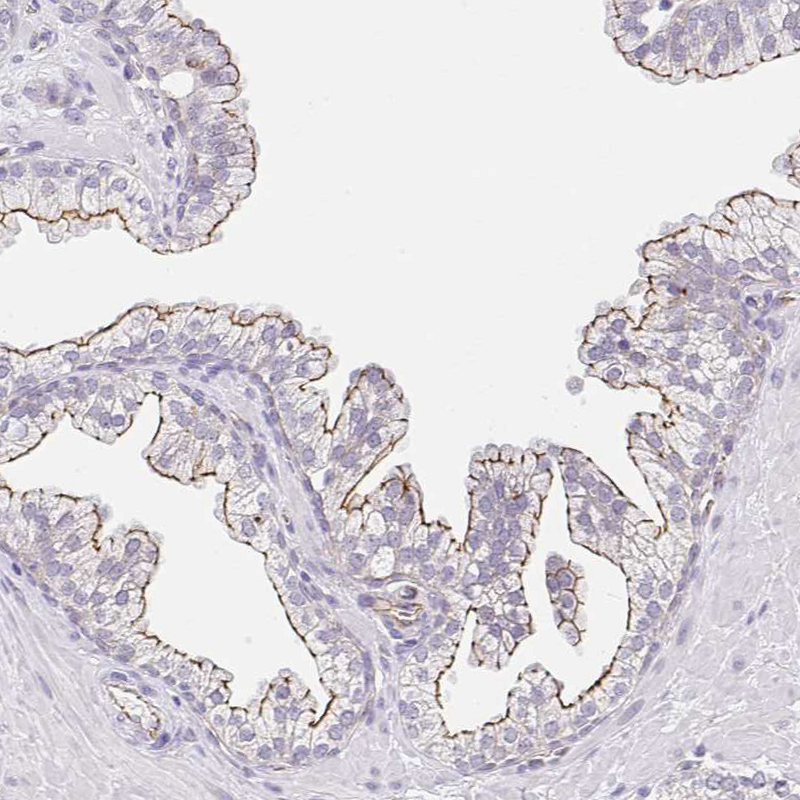

Immunohistochemical staining of human stomach shows strong membranous positivity in glandular cells.